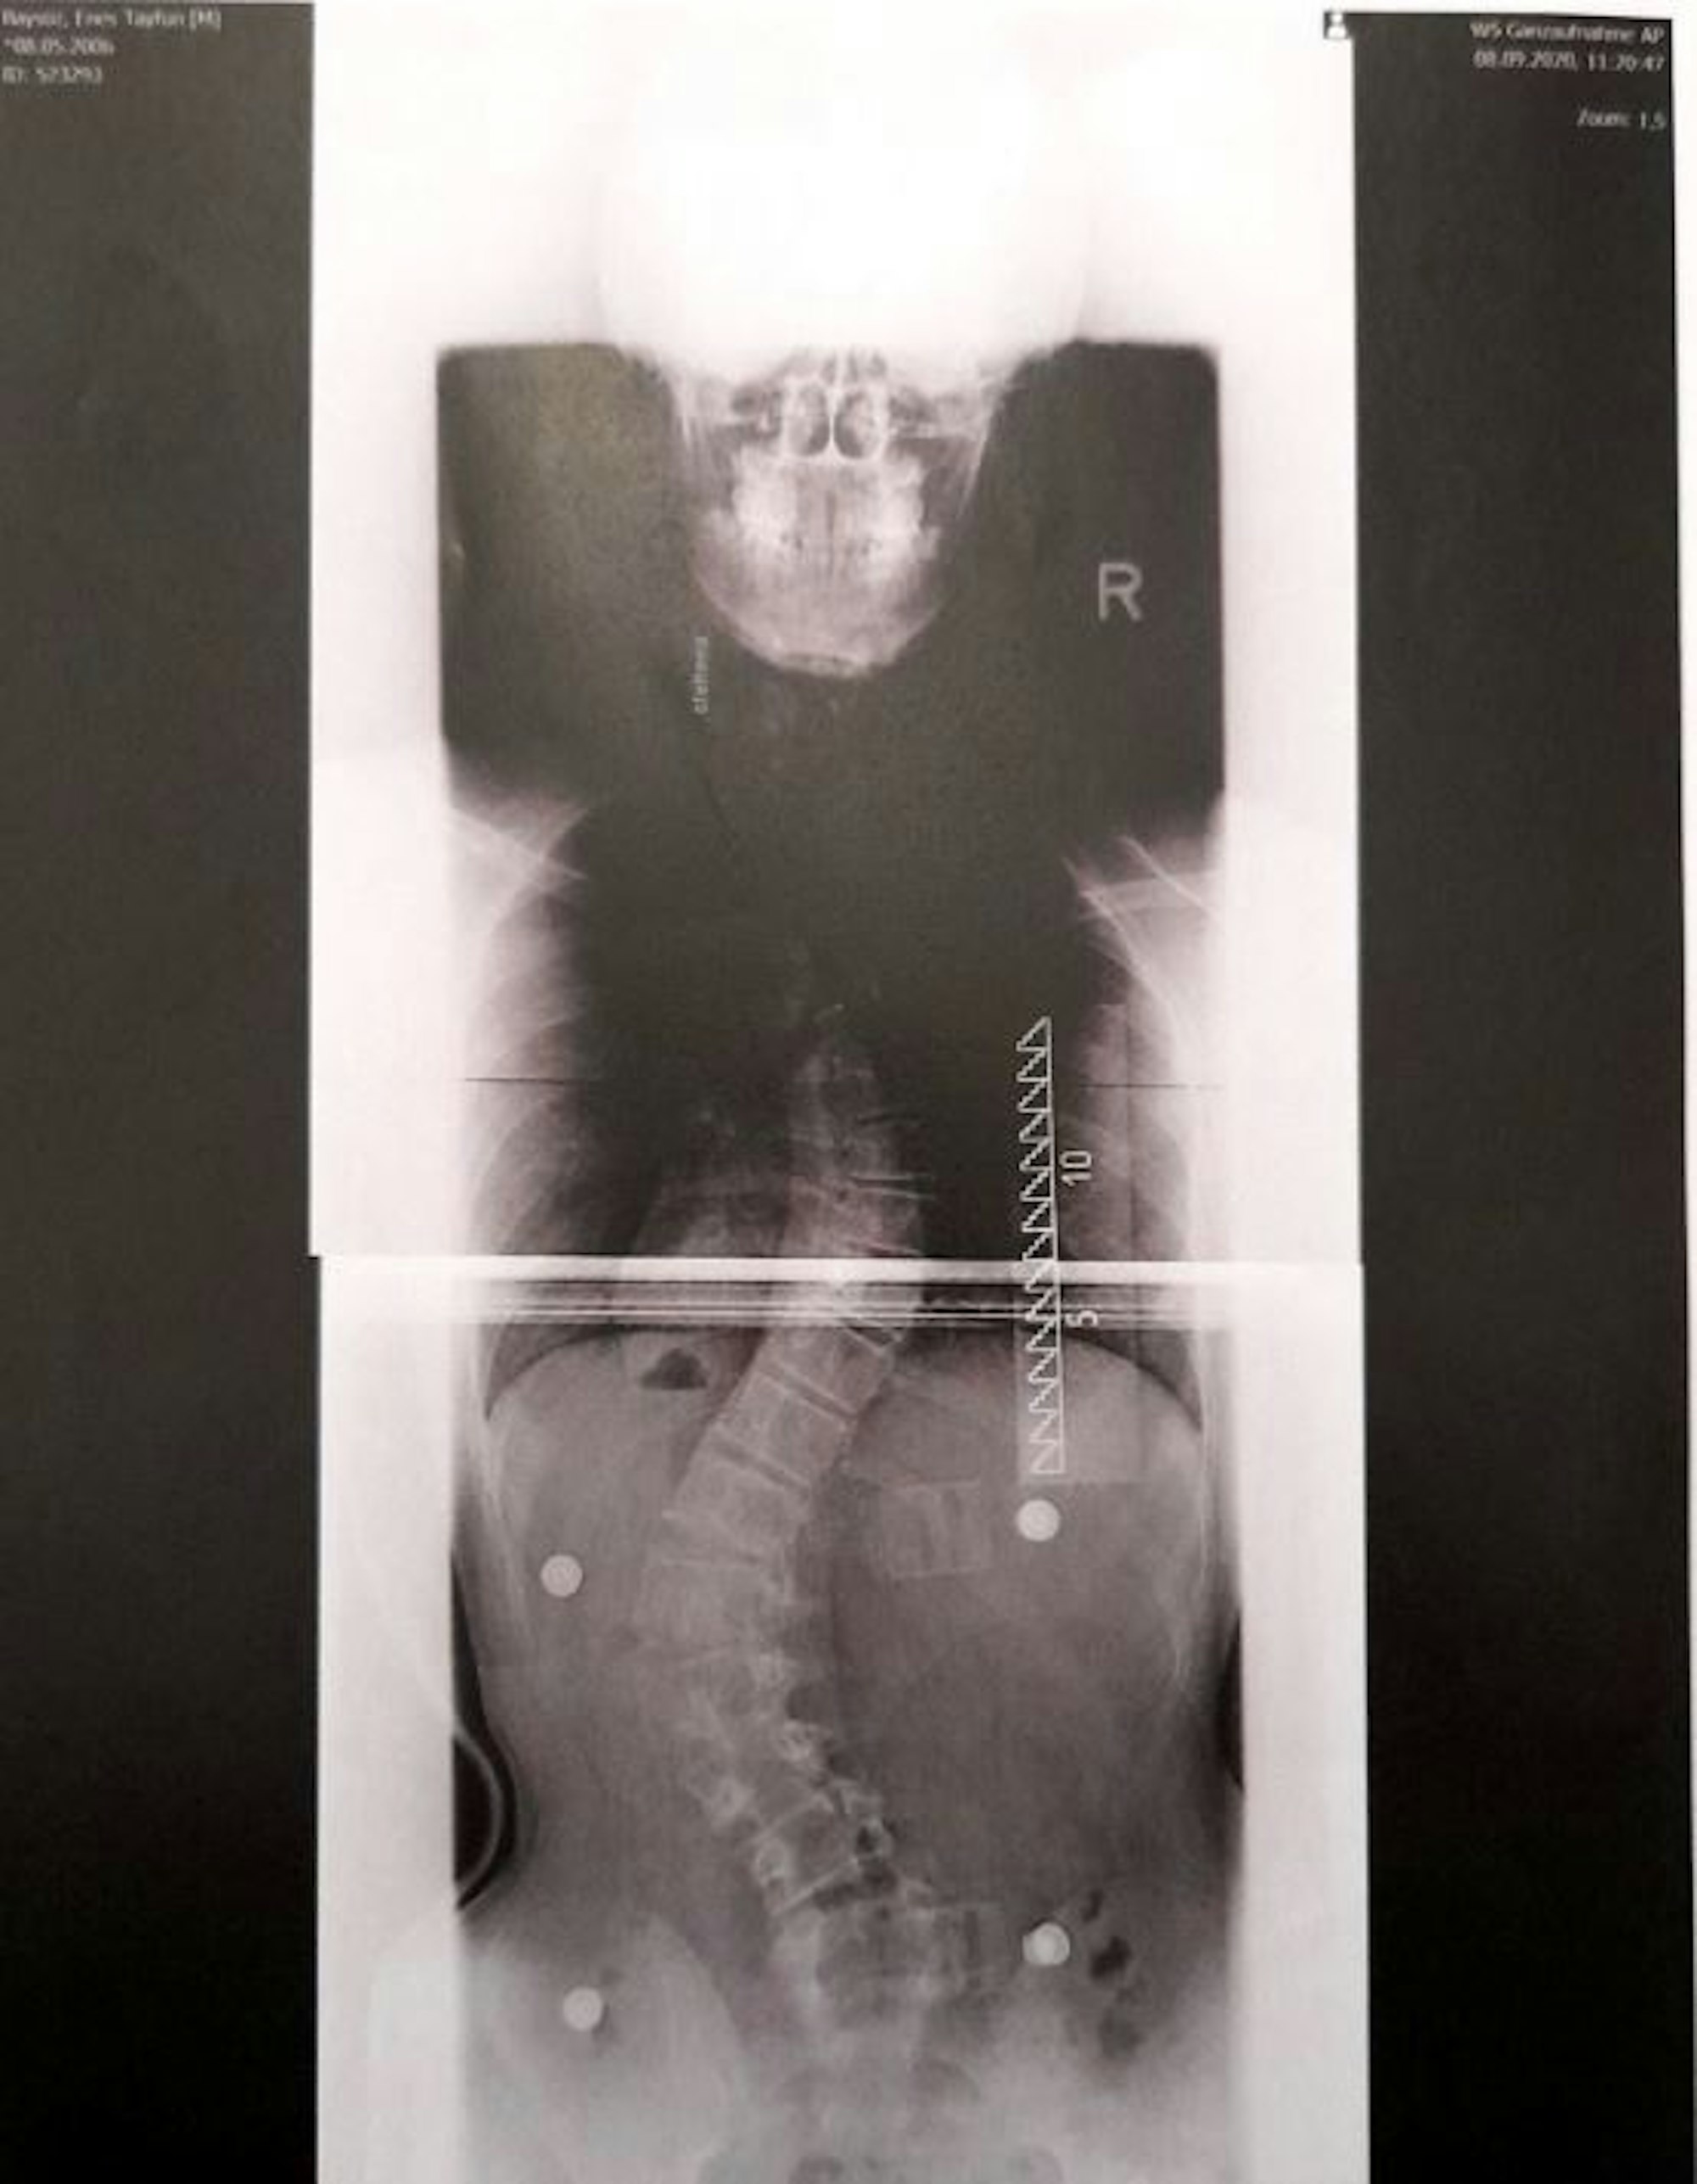

Köln – Es ist ein schweres Schicksal für den 14-jährigen Enes Baysöz aus Köln. Der junge Mann aus Ossendorf leidet an einer seltenen Krankheit. Er hat Skoliose. Das bedeutet, seine Wirbelsäule ist verkrümmt. In seinem Fall um über 60 Grad.

Röntgenaufnahmen zeigen das Ausmaß, das für das bloße Auge kaum zu erkennen ist. Das kann lebensgefährlich sein, da dadurch die Organe erdrückt werden können. Die Krankheit kann aber mit einer teuren Operation behandelt werden. So fing für die Kölner Familie der Kampf um die Kostenübernahme an.

Mittlerweile ist die Wirbelsäule von Enes oben 55 Grad und unten 61 Grad verkrümmt. Enes ist geplagt von ständigen Schmerzen, trägt ein Korsett, das seine Haltung unterstützt. Termine bei der Krankengymnastik gehören zum Alltag des Jugendlichen.

Diese Röntgenaufnahme vom September 2020 zeigt, wie sehr die Wirbelsäule des Kölners Enes Baysöz verkrümmt ist.